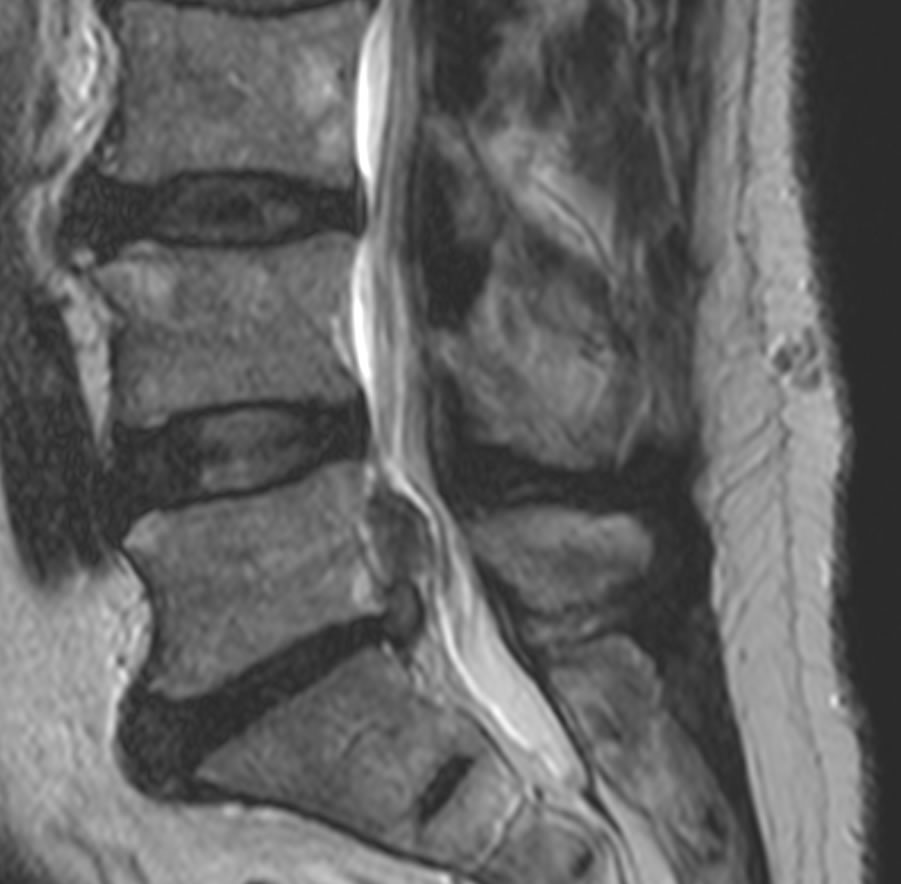

L'investigation principale est l'IRM de la colonne soit lombaire pour les hernies discales lombaire ou cervicale pour les hernies cervicales. Parfois il est utile de faire un éléctroneuromyogramme (ENMG) qui permet d'évaluer le degré d'atteinte de la conduction nerveuse.